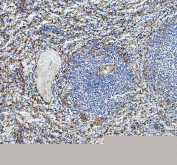

Western blot testing of HUVEC lysate with SELP antibody. Expected molecular weight: 86-140 kDa depending on glycosylation level.